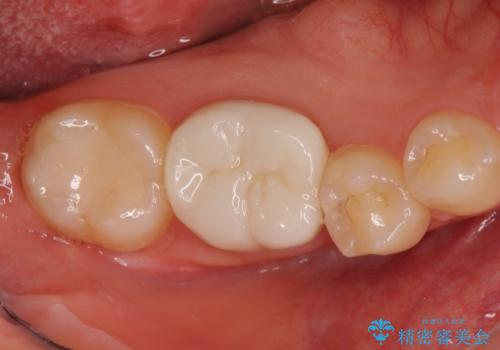

金属ではなく、白い修復物を希望されたため、セラミッククラウンで治療することにしました。

その際、舌側の歯の高さがなく歯肉に埋もれ気味だったっため、奥の親知らずをぬくついでに予め歯周外科処置(要は歯の周りの組織の手術という意味です)を行い、歯ぐきの高さを下げました。

右下7番の虫歯の範囲は咬合面だけだったため、詰め物(セラミックインレー)で治療しました。

- 右下7:セラミックインレー 7.7万円 右下6:ジルコニアクラウン12.1万円、仮歯1.1万円、歯周外科処置16.5万円費用は治療当時の料金となります

下に親知らずがある場合、奥歯の高さを出す手術は親知らずを抜くのと同時に行うことができますので1度で大きく歯ぐきを下げることができます。